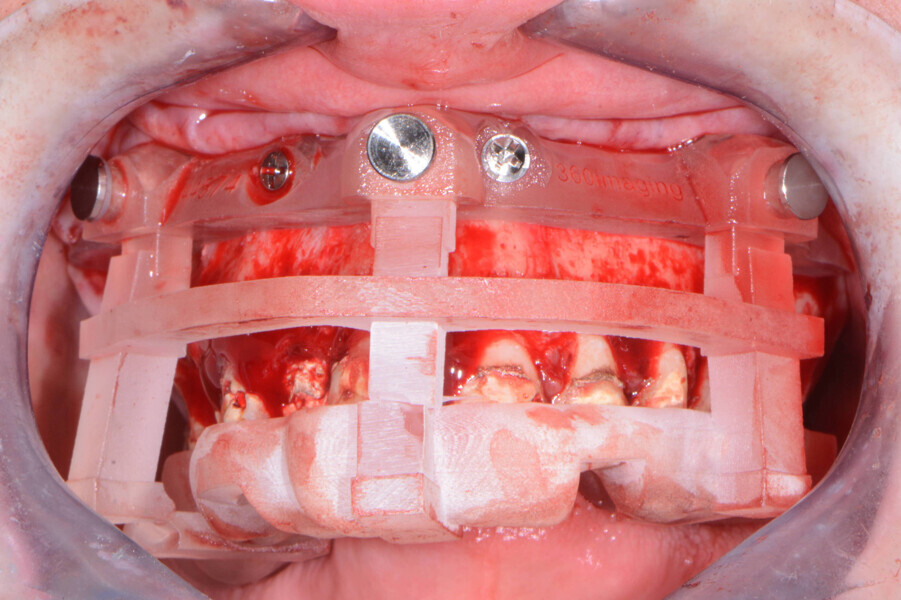

Once the virtual plan had been orchestrated by the laboratory and fully confirmed by me, the next appointment was for the planned surgery with all the necessary components for the guided surgical approach. The patient was appropriately sedated with intravenous medications, and local anaesthesia was administered in both arches. The tissue was then reflected using the Reflector instrument (GoldenDent) so that the bone levelling surgical guide would be fully seated and fixed with its respective retention screws (Figs. 6 & 7). After the positioning of the surgical guide, the maxillary teeth were atraumatically extracted from anterior to posterior utilising the Physics Forceps (GoldenDent). Using a bone reduction bur in the surgical handpiece and motor (Aseptico) with ample irrigation, the maxillary ridge was trimmed to the level indicated by the guide. Once the appropriate bone levelling had been accomplished with the surgical handpiece, the implant surgical guide (Fig. 8) was positioned into the bone levelling guide and the osteotomies for the implants were initiated with a designated pilot drill in the implant system’s guided surgery drilling kit (Adin Dental Implant Systems; Fig. 9).

Fig. 6: Positioning guide.

Fig. 7: Maxillary bone levelling foundation guide.

Fig. 8: Maxillary implant surgical guide.